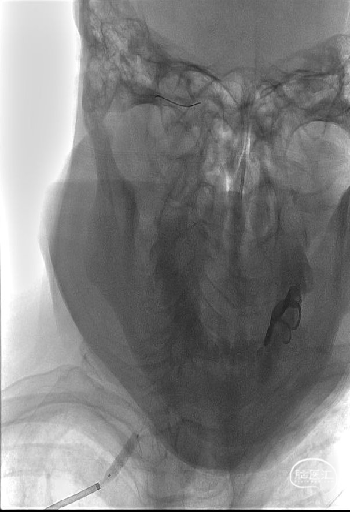

沿泥鳅导丝将6F 95cm远端通路导引导管送至右侧椎动脉开口近狭窄处,撤出泥鳅导丝,在路途下,将0.014inch 180cm导引导丝超选至右侧椎动脉V3段远端,沿微导丝将Bridge椎动脉雷帕霉素靶向洗脱支架送至右侧椎动脉V1段狭窄处,支架释放之前再次通过显影点,确认支架位于合适位置,排气后,以10-15s/atm缓慢加压至10atm打开输送系统球囊以扩张支架。

造影示支架完全覆盖狭窄段,与血管壁贴合良好。复查脑血管造影颅内远端血流通畅。